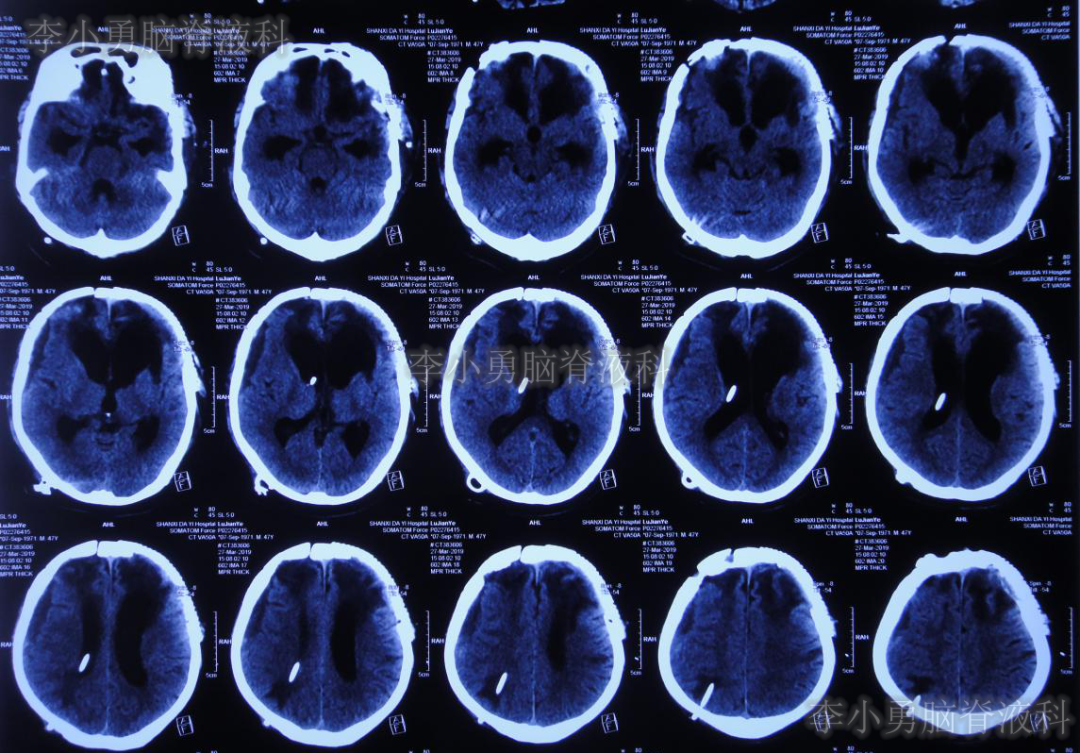

2019年4月22日即脑室-腹腔分流术后34天,第3家医院住院第2天再次出现发热38.6℃,并行头颅CT(图-6)检查示仍为脑室引流术后状态;但胸部CT(图-7)检查示肺炎。

图-6:2019年4月23日头颅CT

虽然已显示出脑积水加重的表现,但医生仍考虑发热为肺部感染引起,因此给予抗菌素治疗2月余。但发热仍难以控制,并且患者意识也逐渐恶化至昏迷的状态,肢体活动亦明显减少。2019年7月2日(颅骨修补术+脑室-腹腔分流术后105天)复查头颅CT(图-8)示脑室进一步扩大。无奈此时再次给予腰椎穿刺,但脑脊液化验仍不支持“颅内感染”。

图-8:2019年7月2日头颅CT